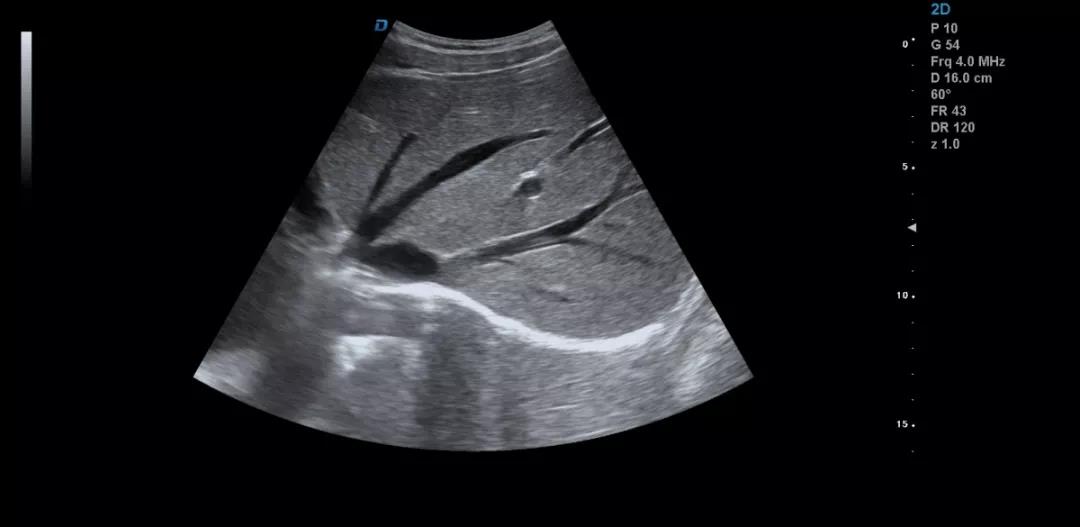

眾所周知,肝臟有很多檢查死角,成為超聲檢查的盲區(qū),如肺和骨所掩蓋處,肝右前上段及右后上段的膈頂部,左外葉外側(cè)角區(qū),沿肝臟表面的肋骨下區(qū)等等部位,只有極其細(xì)致的檢查配上精巧的手法才能盡可能的顯示清楚這些部位。

如果我們能夠細(xì)致的檢查每個病人,所謂的肝臟死角能夠盡可能的探測到,肝臟的死角其實只有膈頂部,其他的部位如果能細(xì)致檢查都可以探測到。

肝臟膈頂部掃查體會:

1)一般是讓患者深吸氣,讓肝臟下移,然后探頭盡量上翹;

2)當(dāng)然很多患者因肥胖或肺氣的干擾會顯示更差,這時我就讓患者深呼氣,把氣全部吐干凈,然后屏氣掃查;

3)還有就是不要沿著肋間隙掃查,而是和肋間隙成一定的角度緩慢向右上方腋前線掃查;

4)在平臥位掃查時,在橫切腎臟時探頭盡量上翹,甚至與腹壁平行,當(dāng)然在右側(cè)肋緣下也行;

5)變換體位掃查,肝臟因重力作用產(chǎn)生移位。左側(cè)臥位、右側(cè)臥位、各種斜位、還有站立位等等。

掃查肝臟時要配合患者的呼吸運(yùn)動,采取你動我靜,你靜我動的掃查方法,并最大限度的側(cè)動探頭,最大角度的顯示肝臟。

發(fā)現(xiàn)肝臟病變時要多切面多角度掃查,可以了解病變的解剖位置并排除假陽性。